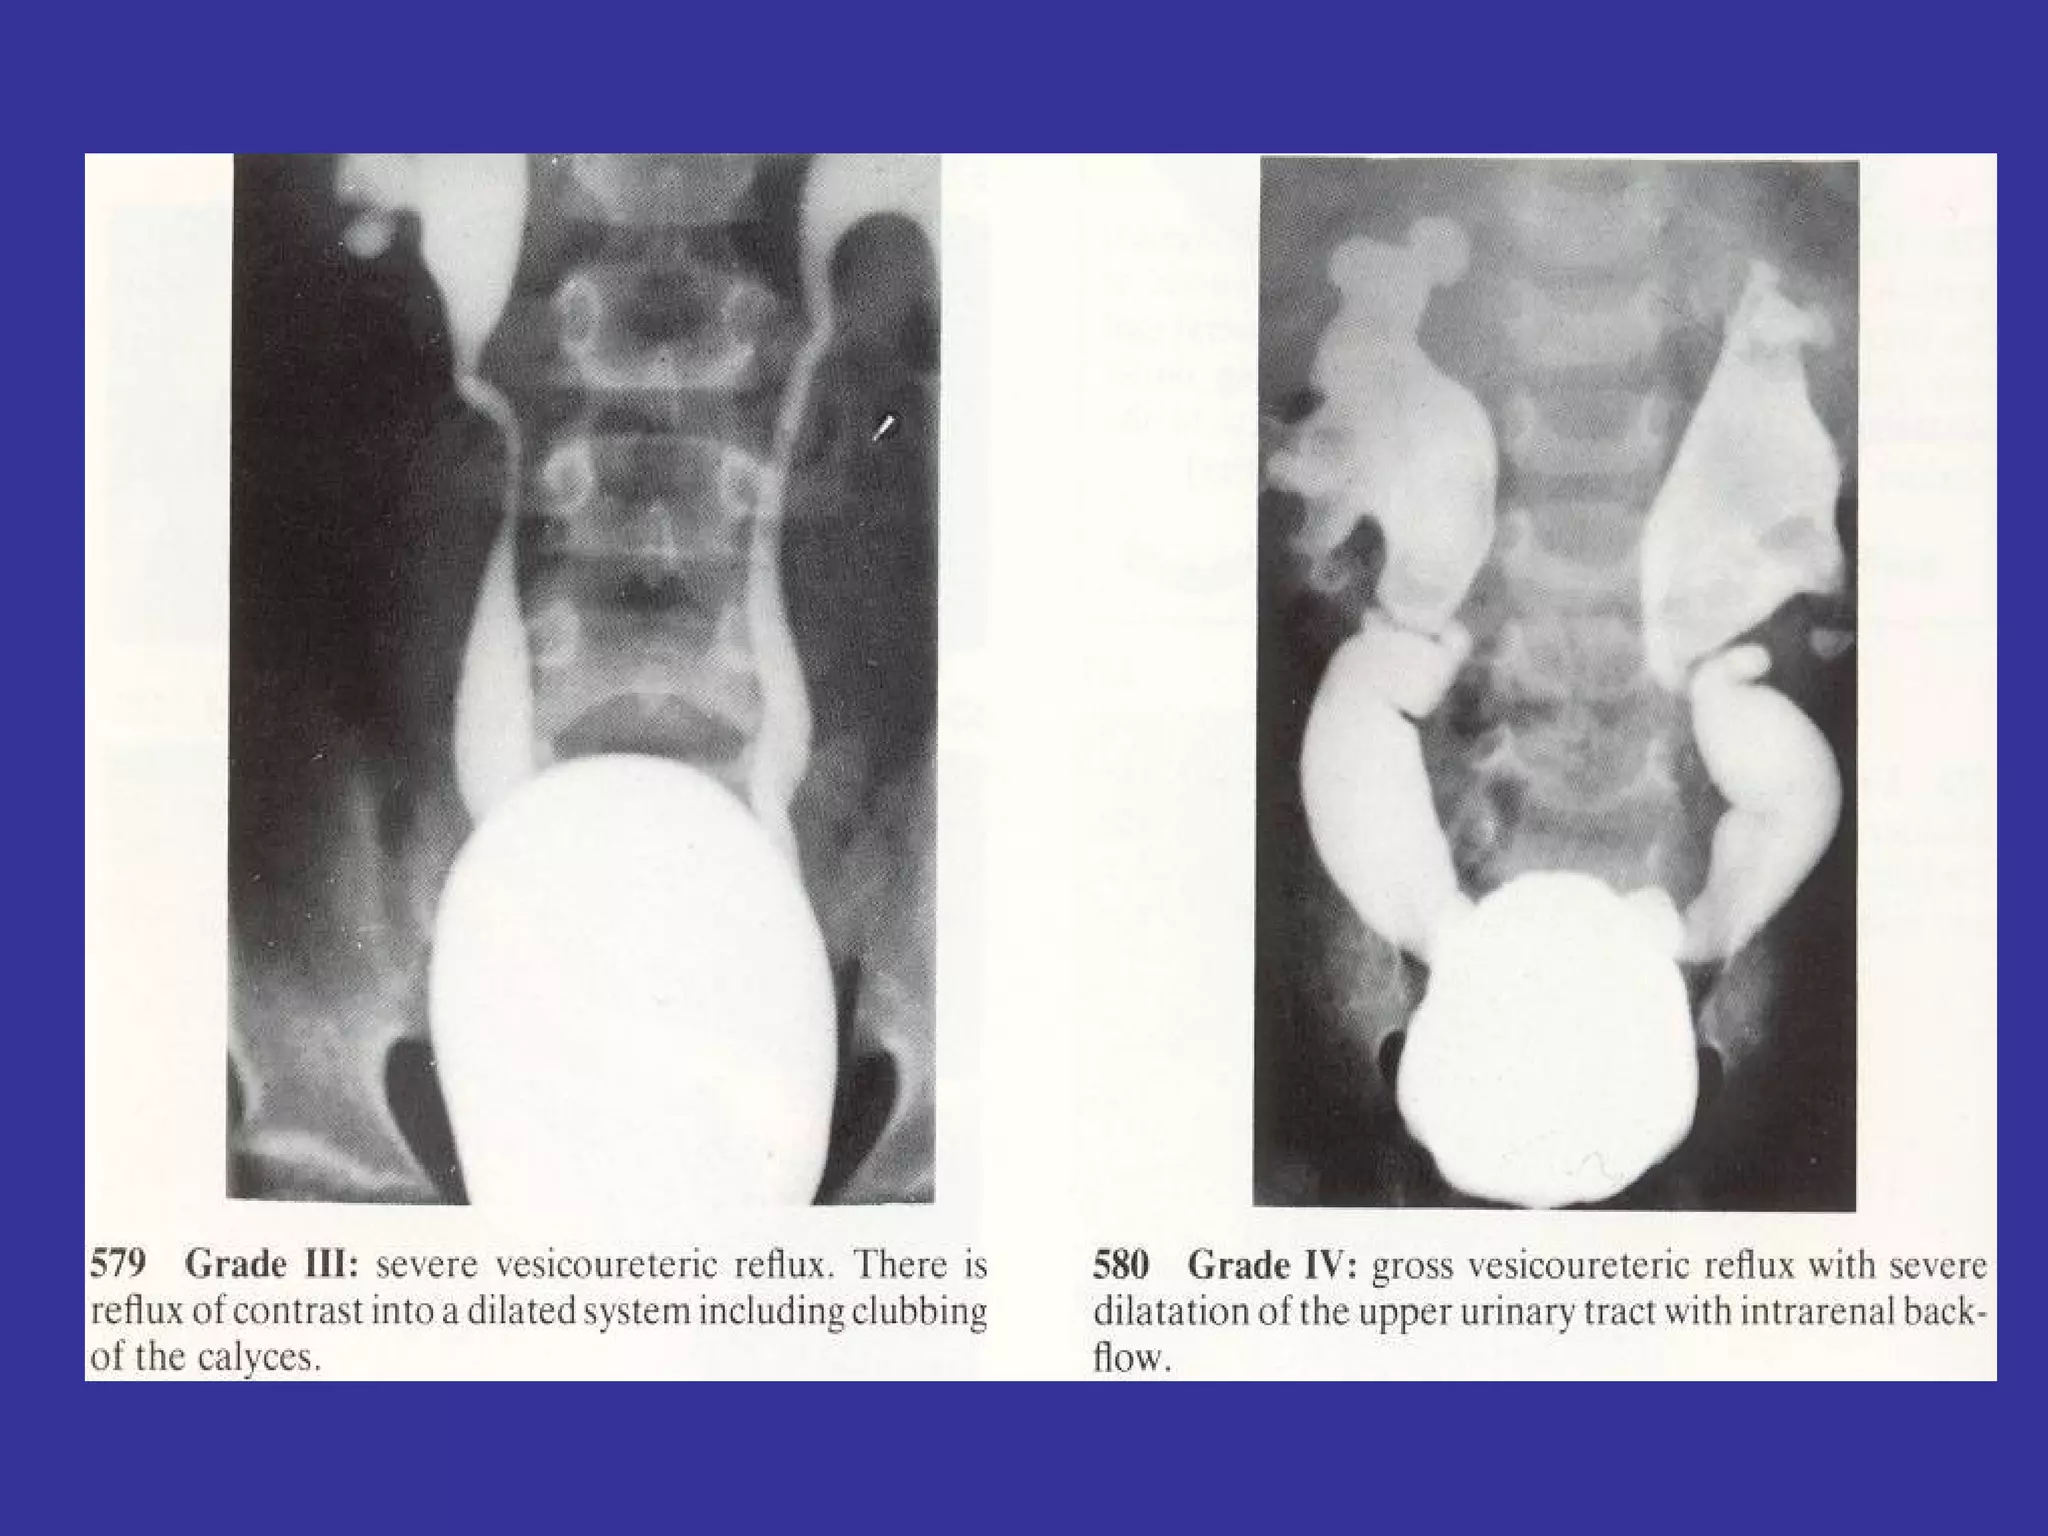

VESICO-URETHERAL REFLUX Is the passage of urine from the bladder to the renal pelvis, secondary to an incompetent  valvular mechanism at the uretero-vesical junction Epidemiology:   Family factors- 34% found to have VUR.  Classification:  REFLUX: Grade  I-   Into a non-dilated distal ureter Grade II-   Into the upper collecting system, with normal calyceal  and no dilatation Grade III-  Mildly dilated/tortuous ureter, with mild blunting of calyceal  Grade IV-  Grossly dilated ureter, moderate dilatation/tortuosity of ureter.  Grade V-   Massive reflux with gross ureteral dilatation and tortuosity of ureter S/S:   UTI sx,  HTN,  Abdominal mass secondary,  Hydronephrosis,  FTT, Enuresis LAB:   Voiding cystourethrogram (VCUG)-  Gold  standard Renal U/S- detects hydronephrosis DMSA renal scan- detects renal  scarring DMSA: Dimercaptosuccinic  acid

VESICO-URETHERAL REFLUX Isthe passage of urine from the bladder to the renal pelvis, secondary to an incompetent valvular mechanism at the uretero-vesical junction Epidemiology: Family factors- 34% found to have VUR. Classification: REFLUX: Grade I- Into a non-dilated distal ureter Grade II- Into the upper collecting system, with normal calyceal and no dilatation Grade III- Mildly dilated/tortuous ureter, with mild blunting of calyceal Grade IV- Grossly dilated ureter, moderate dilatation/tortuosity of ureter. Grade V- Massive reflux with gross ureteral dilatation and tortuosity of ureter S/S: UTI sx, HTN, Abdominal mass secondary, Hydronephrosis, FTT, Enuresis LAB: Voiding cystourethrogram (VCUG)- Gold standard Renal U/S- detects hydronephrosis DMSA renal scan- detects renal scarring DMSA: Dimercaptosuccinic acid